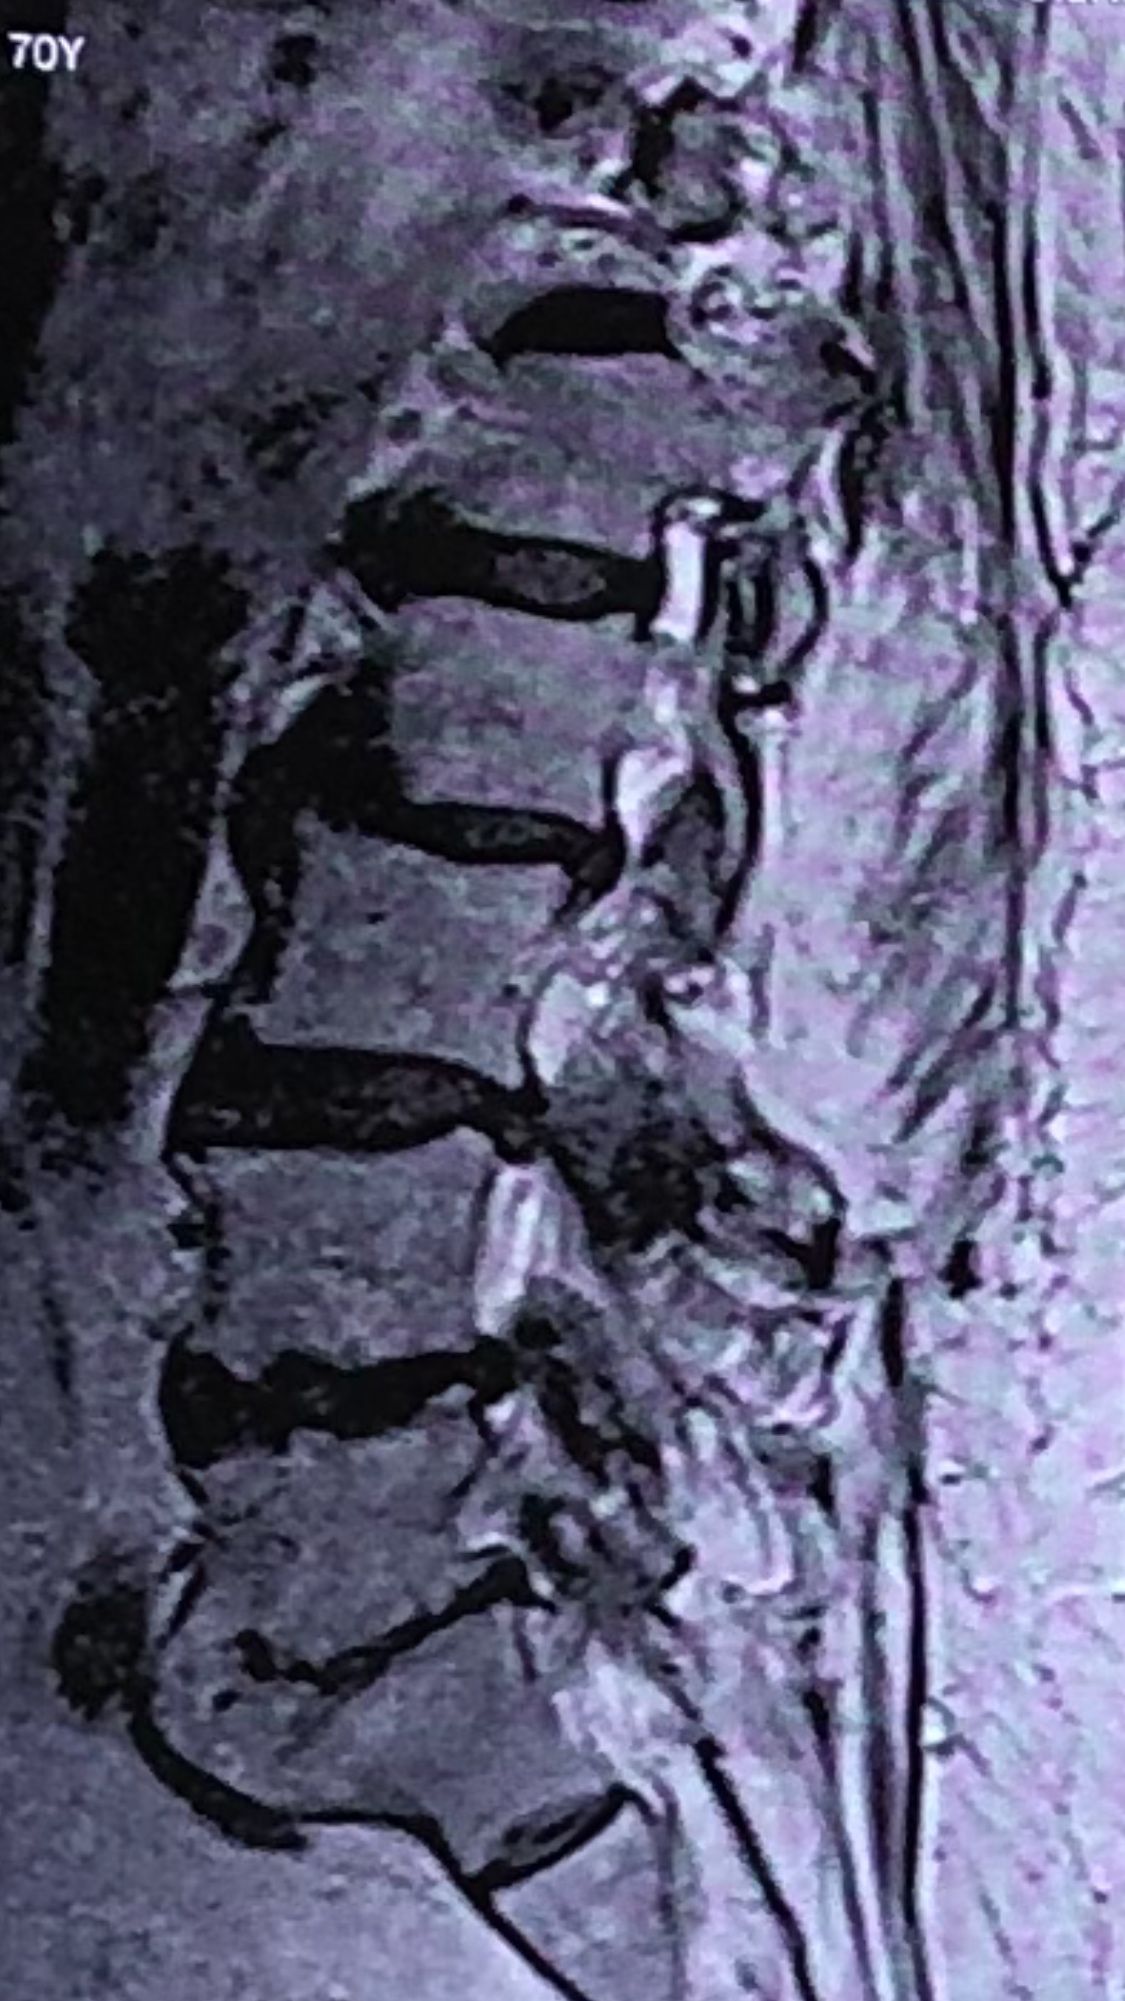

70 yrs old female presented to my clinic today (Oct 06/2024)due to severe LBP with both legs pain for several years.

7 years ago came to my clinic with L leg radicular pain and I referred her to a neurosurgeon. Patient underwent full laminectomy from L1 to S1. Few months after surgery her LBP and legs pain were started and hasn’t improved since then. Now walking aggravates the pain and forces her to bend forward. Patient had mri from 6 months ago. Her mri 7 years ago was similar to the recent mri, just laminectomy and soft tissue collection has been added. In neurological examination p.tvdid not have any neurological deficits. I ordered lower limbs emg/ncv, dynamic lumbar spine X.ray. As a chiropractic Doctor what would be your plan of management for this patient?